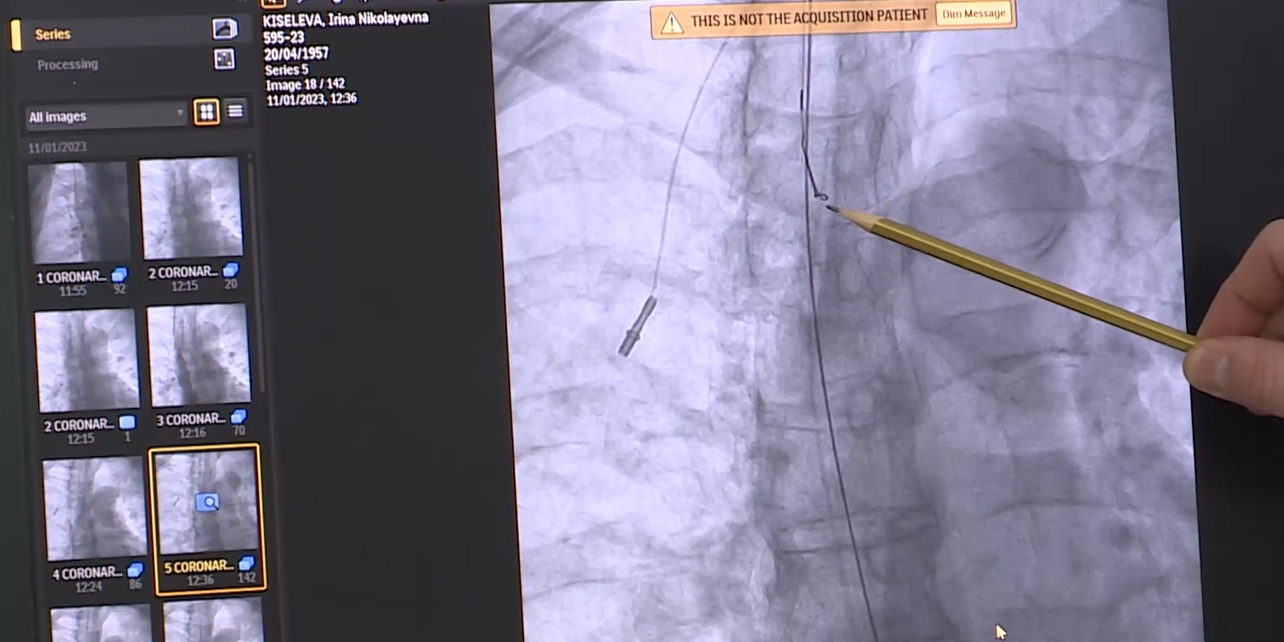

У орловчанки, которая много лет борется с онкологическим заболеванием, отломилась часть катетера — через него женщина получала химиотерапию, и ушел в предсердие. Орловские хирурги сами сделали сложнейшую операцию по извлечению инородного тела. Об этом пишет ОГТРК.

Хирург Алексей Середицкий и его коллеги решили проводить малоинвазивную операцию с помощью аппаратов рентгена и УЗИ. На операции выяснилось, что часть катетера вросла в правое предсердие, но с хирурги справились с осложнением.